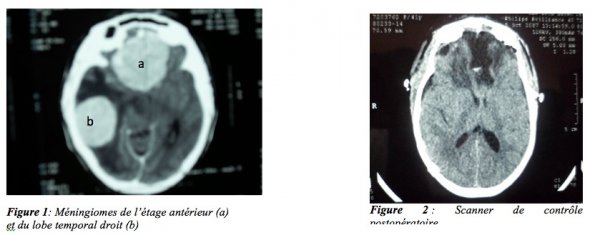

Ces lésions sont évocatrices de méningiomes cérébraux. Une indication opératoire a été retenue. L’intervention réalisée en deux temps, à quinze jours d’intervalle, a consisté en l’abord successif de la lésion pétreuse puis de la lésion de l’étage antérieur. Les examens anatomopathologiques postopératoires ont confirmé le diagnostic de méningiomes. Les suites opératoires ont été excellentes avec disparition complète des céphalées, des troubles visuels et neurologiques, autorisant une complète autonomie et la reprise des activités professionnelles au bout de six mois. Le bilan neuro- radiologique de contrôle a confirmé l’exérèse complète des deux lésions. (Figure 3).